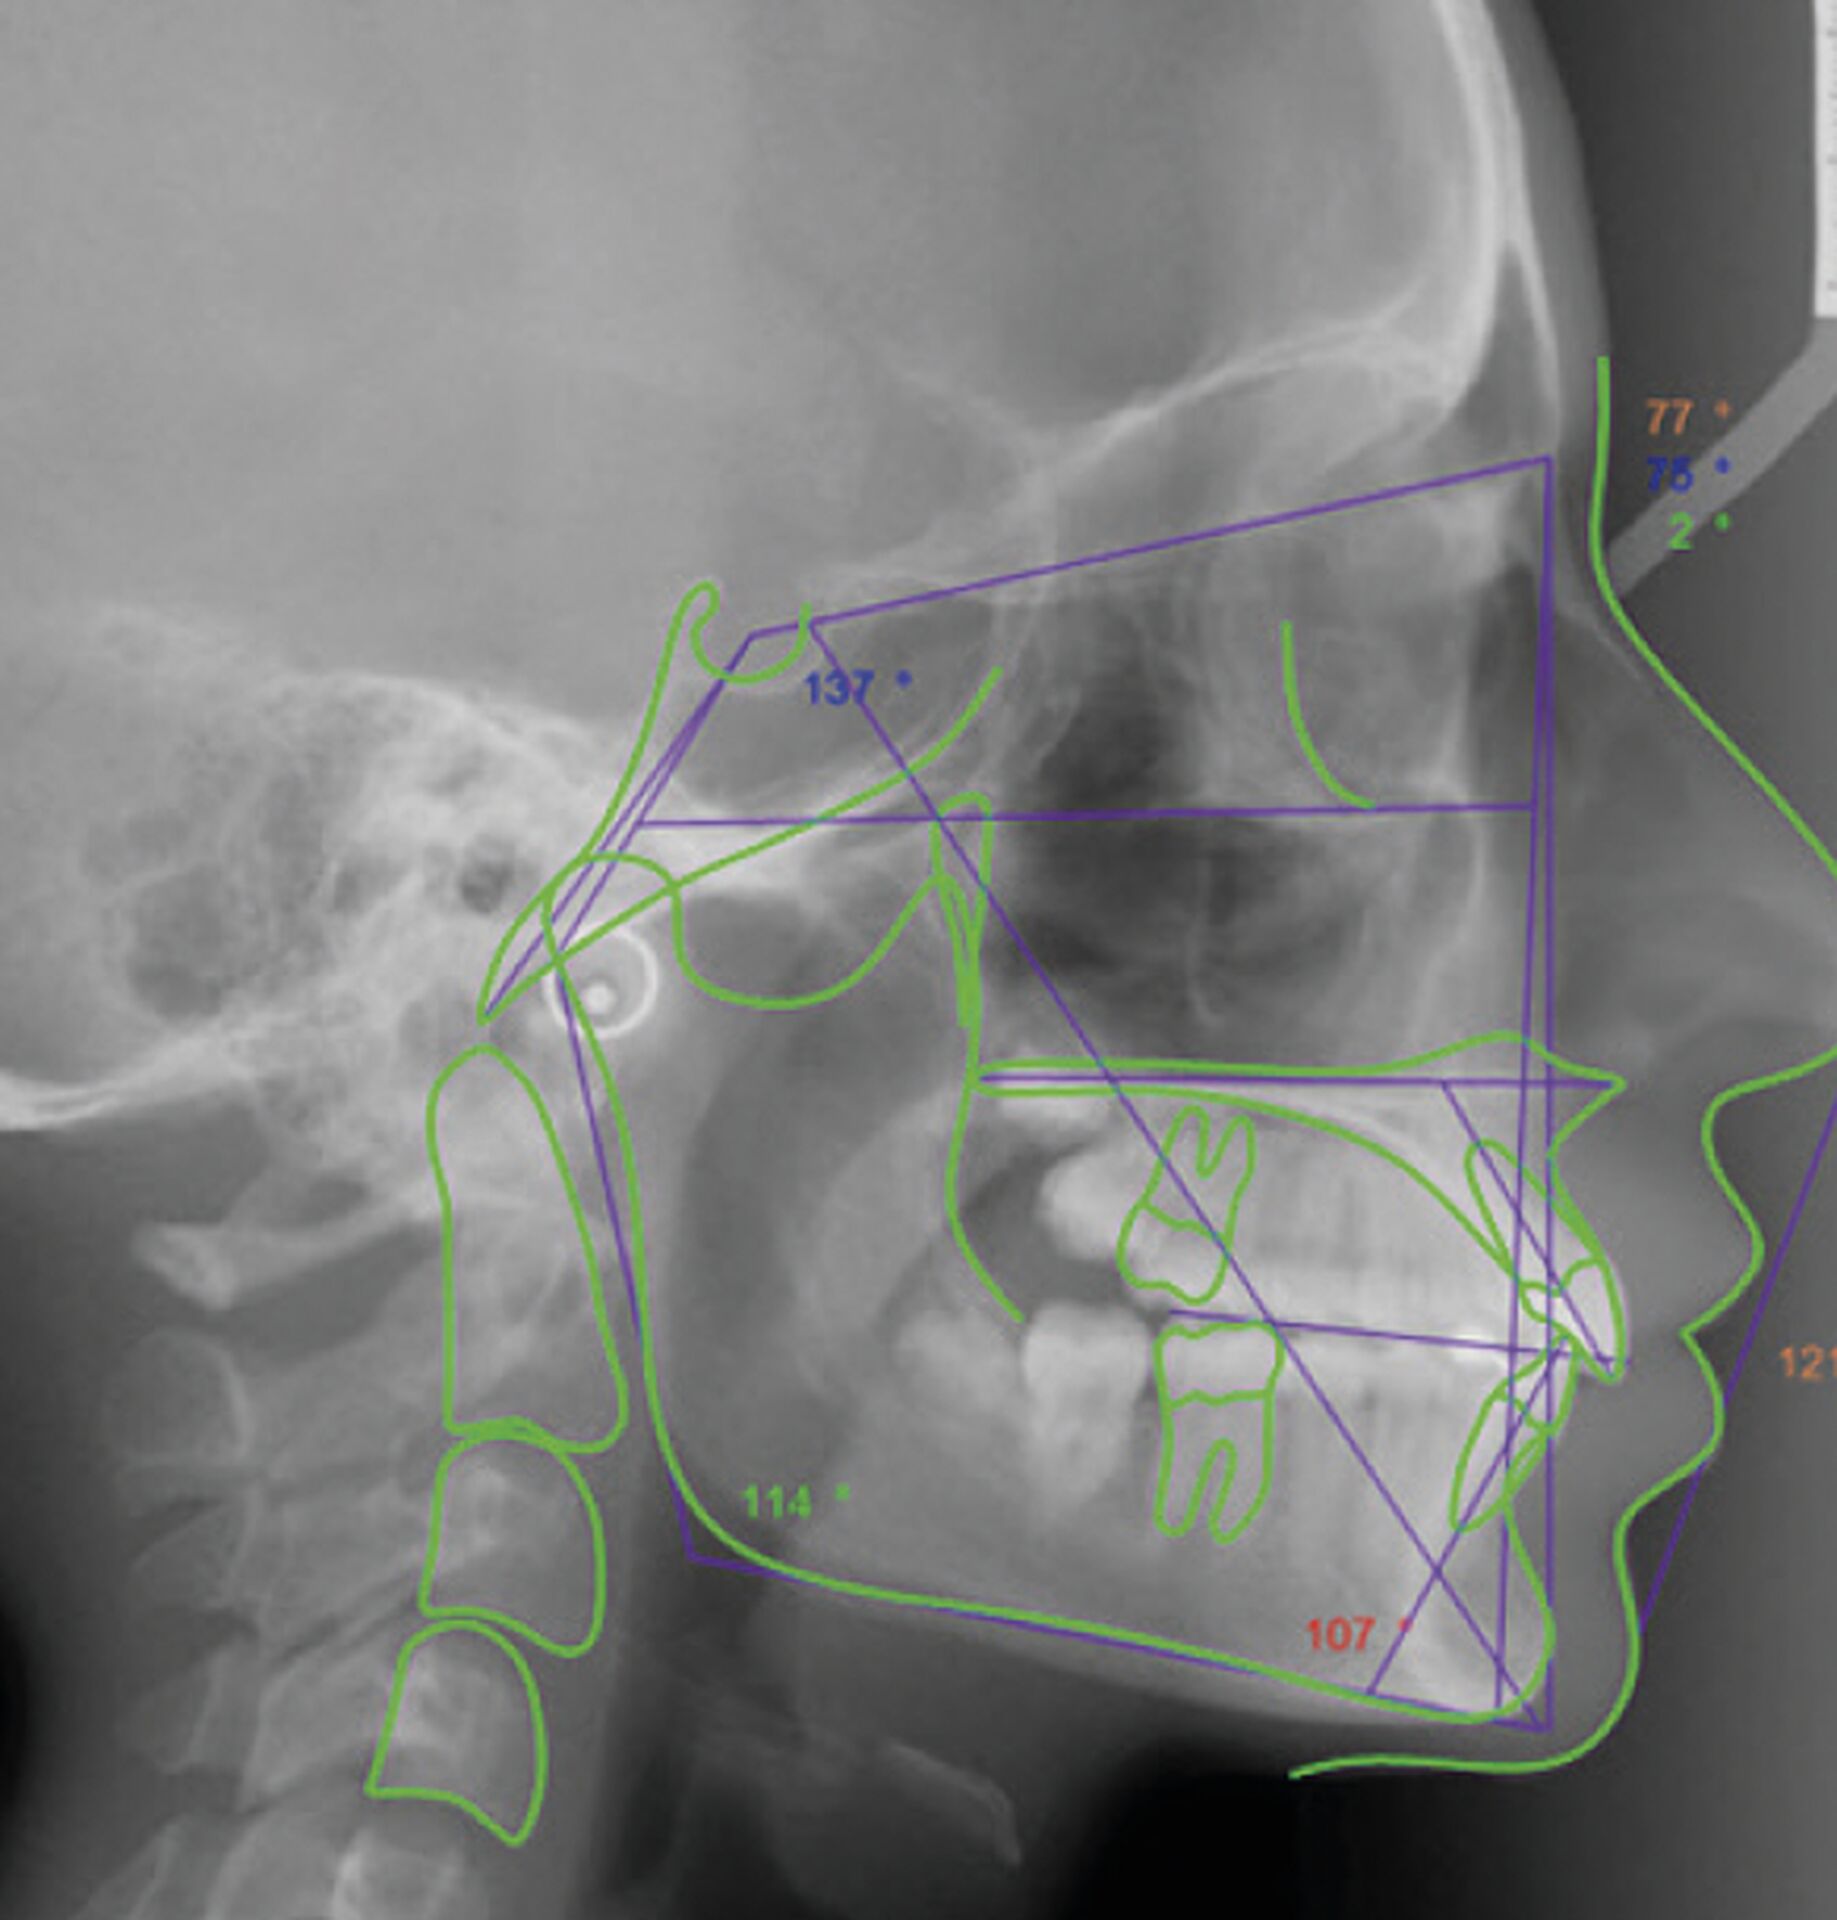

Le logiciel offre une analyse et superposition d’images automatique ou manuelle, permettant de comparer l’évolution du patient et de générer des rapports détaillés. La fonction de projection de croissance simule l’évolution crânienne de l’âge squelettique actuel à un âge futur, offrant une vision prospective du développement du patient jusqu’à la maturité.

Ceph Analysis intègre également des outils de planification de traitement basés sur les prévisions VTO (Visual Treatment Objective) et STO (Surgical Treatment Objective). Ces fonctions permettent de simuler des traitements orthodontiques ou chirurgicaux et d’obtenir des prévisions fiables selon la rigidité des tissus, facilitant ainsi la création de plans de traitement optimisés.

• Plus de 200 types d’analyses céphalométriques intégrées et personnalisables